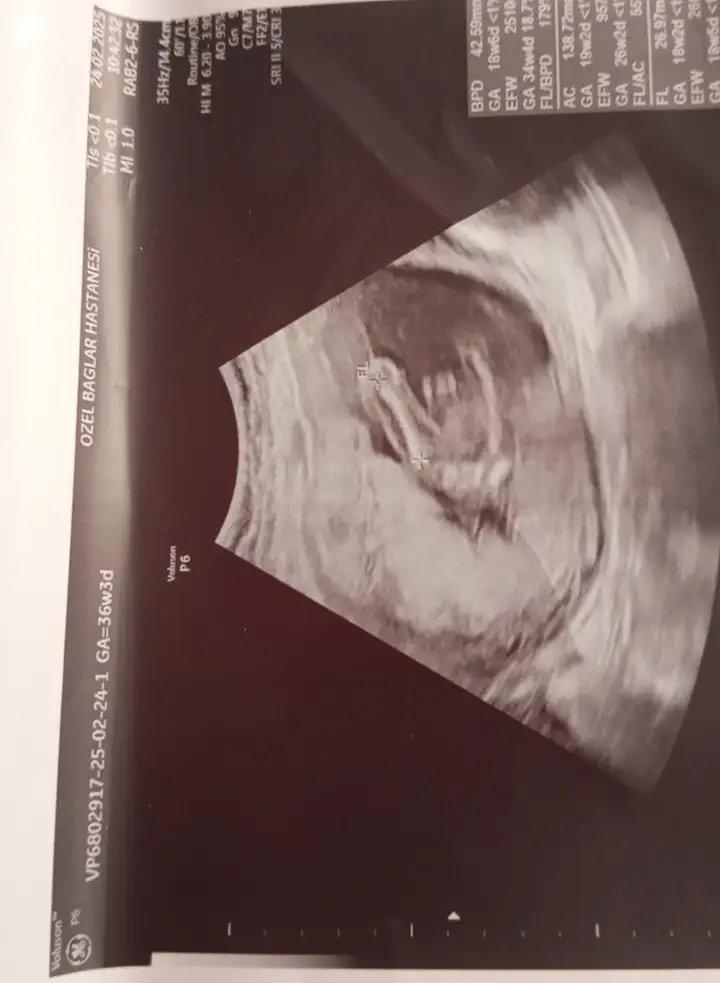

Bunlarada bakar mısınız lütfenErkek canım

Bunlarada bakar mısınız lütfenEvet erkek bu bebiş

Bunlarada bakar mısınız lütfenNub teorisi benim 2 oğlumda doğru çıktı. Bu bebiş kıza benziyor

Nub teorisi benim 2 oğlumda doğru çıktı. Bu bebiş kıza benziyor